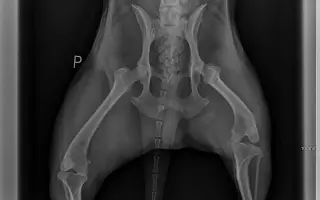

Pomozte Dirkovi změnit tento příběh